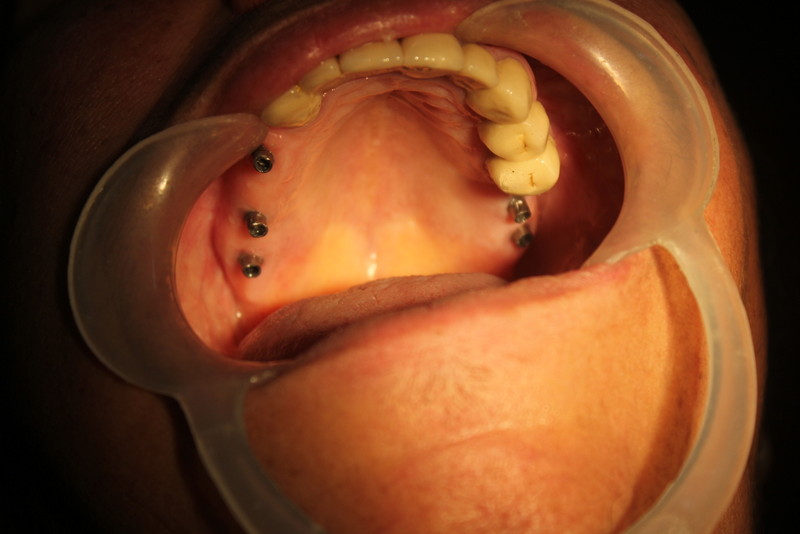

Bilateral Direct Sinus Lifts